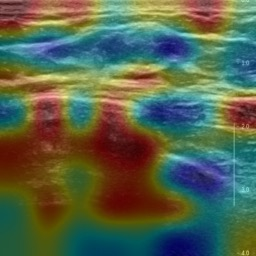

Ultrasonography is an important routine examination for breast cancer diagnosis, due to its non-invasive, radiation-free and low-cost properties. However, it is still not the first-line screening test for breast cancer due to its inherent limitations. It would be a tremendous success if we can precisely diagnose breast cancer by breast ultrasound images (BUS). Many learning-based computer-aided diagnostic methods have been proposed to achieve breast cancer diagnosis/lesion classification. However, most of them require a pre-define ROI and then classify the lesion inside the ROI. Conventional classification backbones, such as VGG16 and ResNet50, can achieve promising classification results with no ROI requirement. But these models lack interpretability, thus restricting their use in clinical practice. In this study, we propose a novel ROI-free model for breast cancer diagnosis in ultrasound images with interpretable feature representations. We leverage the anatomical prior knowledge that malignant and benign tumors have different spatial relationships between different tissue layers, and propose a HoVer-Transformer to formulate this prior knowledge. The proposed HoVer-Trans block extracts the inter- and intra-layer spatial information horizontally and vertically. We conduct and release an open dataset GDPH&GYFYY for breast cancer diagnosis in BUS. The proposed model is evaluated in three datasets by comparing with four CNN-based models and two vision transformer models via a five-fold cross validation. It achieves state-of-the-art classification performance with the best model interpretability.

翻译:超声波分析是乳腺癌诊断的一个重要常规检查,原因是其非侵入性、无辐射和低成本的特性。然而,由于其内在局限性,它仍不是乳腺癌的第一线筛选测试。如果我们能够精确地通过乳房超声图像诊断乳腺癌(BUS),它将是一个巨大的成功。我们提出了许多基于学习的计算机辅助诊断方法,以实现乳腺癌诊断/感官分类。然而,其中多数方法需要事先确定性能模型,然后对ROI内部的跨值进行分类。常规分类支柱,如VGG16和ResNet50等,可以在没有ROI要求的情况下实现有希望的分类结果。但是这些模型缺乏可解释性,从而限制了其在临床实践中的使用。在本研究中,我们提出了一个新的无乳腺癌诊断模型,在超声波图像中进行解释性特征描述。我们利用了先前的解剖学学学知识,即恶性肿瘤和良性肿瘤模型在不同组织层之间有着不同的空间关系,并提议采用状态解析法来编制这一先前的知识。拟议中的HOVer-Trans-Trading-Tradef-trainal Ex-deal-dealal-deal-deal-deal-degraphal-deal-deal-deal-deal-deal-deal disal disal-dal-dal-dal-dal-dal-deal-deal-dal-deal-deal-deal-dal-dal-dal-dal-dal-dal-dal-dal-dal-dal-dal-dal-dal-dal-I-dal-Iversal-dal-Ial-d-d-I-d-d-I-I-I-I-I-I-I-I-I-I-I-I-I-I-I-I-I-I-I-I-I-I-I-I-I-Ial-I-Ial-Ial-I-I-I-I-I-I-I-I-I-I-I-I-I-I-I-I-I-I-I-I-I-I-I-I-I-I-I-I-I-I-I-I-